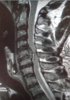

I never would guess that overhead pressing could herniate several cervical disks like that. Glad to see you're doing good man!